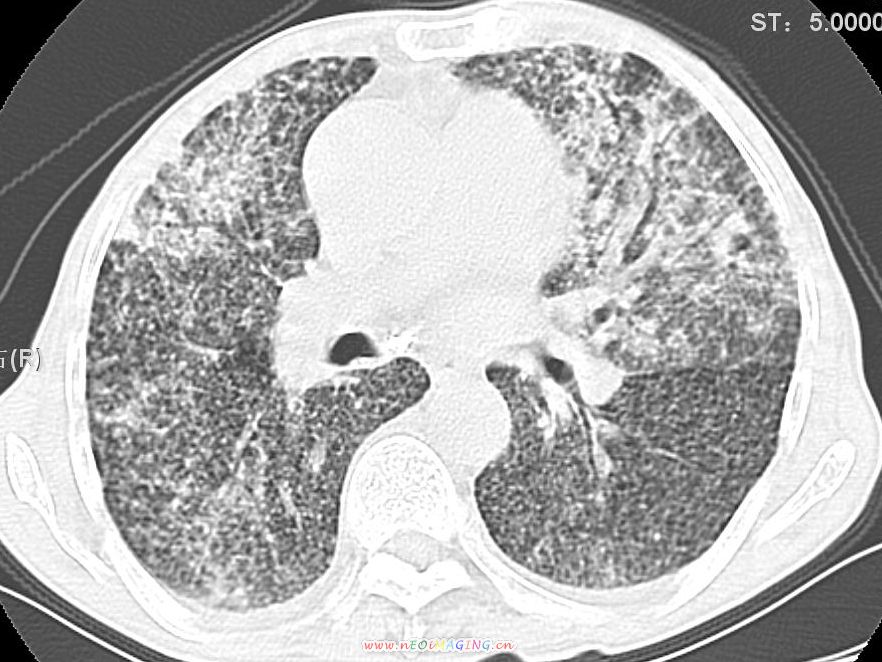

患者咳嗽月余,高热数天,咳黄色稍脓痰。

双肺野分布多个小结节状高密度影,其内散在斑片状模糊影,气管。支气管通畅,纵隔内淋巴结钙化,胸膜局限性增厚粘连,胸腔少量积液。结合病史考虑结核并感染的可能性大,胸膜炎并积液。肺泡癌待排。

纵隔内见钙化的淋巴节,上肺见钙化灶,双肺均匀弥漫分布小结节影,边缘较清楚,能不能考虑是在矽肺的基础上并发的结核和感染,请详细了解病史结合临床.